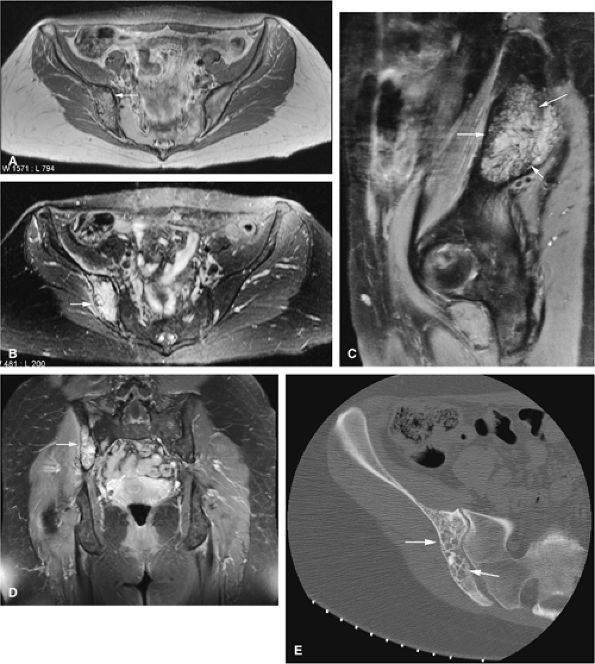

![]() |

FIGURE 14-5 ● FDG-PET in the evaluation of patients with sarcomas. Whole-body FDG-PET scan (A) and corresponding axial image (B) in a patient with neurofibromatosis type 1 demonstrates a region of intense FDG uptake in the right buttock area (arrow), which was found to represent a malignant peripheral nerve sheath tumor arising in a neurofibroma. (C and D) Images from a whole-body FDG PET scan in a patient with osteosarcoma show intense FDG uptake in the proximal tibia (D) in the area of the tumor (arrow). Images of the chest and abdomen demonstrate no evidence of metastatic disease. A marker was placed over the left chest wall (C) (arrowhead). (E) Coronal, axial, and sagittal images of a whole-body FDG-PET scan in a patient with osteosarcoma of the right femur. The patient underwent resection of the right femur and total knee arthroplasty. MR images and CT scans were deemed inadequate for tumor evaluation because of metallic artifact. FDG-PET scan shows a cold defect in the region of the right knee arthroplasty (arrows) and no increased FDG uptake in the area of the right femur and knee.